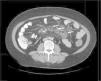

Una vez descartadas infecciones (tuberculosis y enfermedad de Whipple) y una enfermedad de Crohn, se planteó el principal diagnóstico diferencial con el linfoma. Dado el diagnóstico de EC, las características radiológicas de las adenopatías y la localización exclusivamente mesentérica, no se realizó estudio histológico debido a la baja probabilidad de linfoma. Se interpretaron los hallazgos como un SNMC y se decidió dieta sin gluten (DSG) y control radiológico precoz. A los 3 meses, la paciente había ganado 3kg de peso y la TC de control presentó cavitación y reducción de tamaño de las adenopatías, lo que corroboró el diagnóstico (fig. 4).

Posterior al inicio de la DSG se observa una progresiva cavitación de las adenopatías y reducción de su tamaño, lo que constituye un signo patognomónico del SNMC. Además de las restricciones dietéticas típicas de la EC, en ocasiones es necesario el uso intensivo de corticoides sistémicos6. En relación con el pronóstico de esta entidad, si bien publicaciones iniciales describían una mortalidad elevada en pacientes con SNMC, nuevos trabajos han reportado evoluciones similares al resto de pacientes celiacos7.